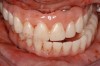

A patient with tardive dyskensia, for example, may experience dramatic changes in expressive facial activity and corresponding dysfunction in the muscle memory needed to repeat a centric position.19,20 Figure 8 and Figure 9 show an 82-year-old patient who had previously been treated for depression, had a failing dentition, and was diagnosed with tardive dyskensia. Extreme uncontrolled contortions of the facial musculature were evident in the patient when attempting to record a high smile line; removal of enough maxillary bone to hide the transition line was impossible. Dramatic compromises in occlusal scheme may be necessary to achieve even a moderately successful result; yet the implant approach realistically may be the only way to offer any functional improvement (Figure 10 and Figure 11).

Fig 8. Failing dentition in an 82-year-old patient currently diagnosed with tardive dyskensia.

Figure 8

Fig 9. Transition line could not be hidden due to uncontrolled contortions of the facial musculature.

Figure 9

Fig 10. Recording a repeatable centric position was virtually impossible for this patient due to spasticity of the masticatory system. Among the compromises necessary in creating an occlusal scheme was to revert to a monoplane approach.

Figure 10

Fig 11. Recording a repeatable centric position was virtually impossible for this patient due to spasticity of the masticatory system. Among the compromises necessary in creating an occlusal scheme was to revert to a monoplane approach.

Figure 11